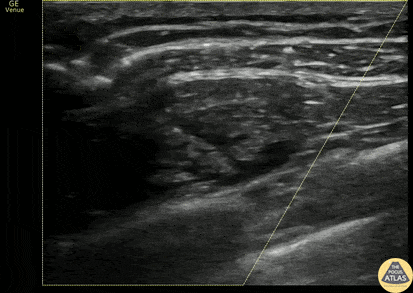

20s M presented after GSW to the chest, and sustained a hemothorax requiring non-emergent chest tube placement. To augment pain control, a serratus anterior plane block was performed with bupivacaine. The block is shown here, with infiltration of the hypoechoic anesthetic deep to the serratus anterior muscle, just above the rib and intercostal muscles. Anesthetic could alternatively be placed in the fascial plane between serratus anterior and latissimus dorsi, which is the fascial plane seen superficial to the anesthetic in this clip. This patient was able to have a chest tube placed with adequate analgesia and without complication and was admitted for further management of his GSW. Dr. Olivia Serigano, PGY4 Denver Health Residency in Emergency Medicine